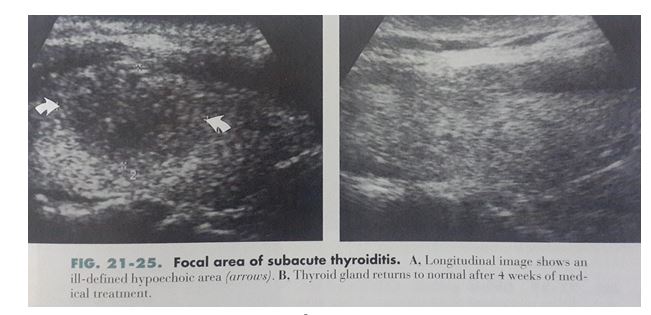

- 2. Viêm tuyến giáp tổ chức hạt bán cấp (Subacute granulomatous thyroisditis): (Hình 9)

– Thường do virus

– Lâm sàng thường có sốt và đau.

– Siêu âm thấy thùy tuyến giáp to ra, giảm echo & giảm mạch máu do phù

– Tăng sinh mạch máu

Hình 9: Viêm tuyến giáp bán cấp